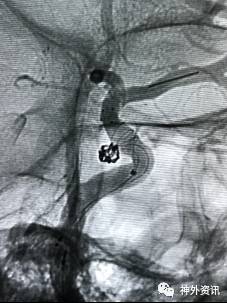

病例一